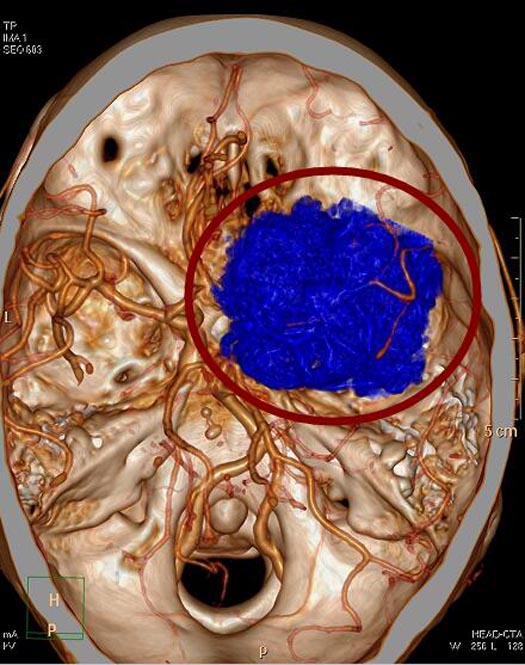

广东三九脑科医院头颅MR检查提示:右侧蝶骨嵴示一跨颅窝生长巨大占位性病变,内示多发流空血管影,大小约为6.4cm×5.2cm×5.4cm。 头颅CTA提示:右侧蝶骨嵴跨前中颅窝巨大占位性病变,血供极其丰富,考虑脑膜瘤。

▲术前CTA